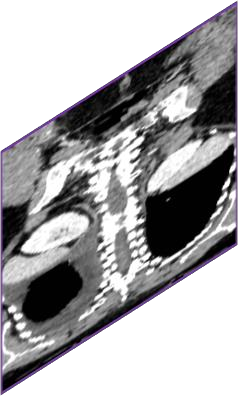

Due to the constraints of the imaging device and high cost in operation time, computer tomography (CT) scans are usually acquired with low intra-slice resolution. Improving the intra-slice resolution is beneficial to the disease diagnosis for both human experts and computer-aided systems. To this end, this paper builds a novel medical slice synthesis to increase the between-slice resolution. Considering that the ground-truth intermediate medical slices are always absent in clinical practice, we introduce the incremental cross-view mutual distillation strategy to accomplish this task in the self-supervised learning manner. Specifically, we model this problem from three different views: slice-wise interpolation from axial view and pixel-wise interpolation from coronal and sagittal views. Under this circumstance, the models learned from different views can distill valuable knowledge to guide the learning processes of each other. We can repeat this process to make the models synthesize intermediate slice data with increasing inter-slice resolution. To demonstrate the effectiveness of the proposed approach, we conduct comprehensive experiments on a large-scale CT dataset. Quantitative and qualitative comparison results show that our method outperforms state-of-the-art algorithms by clear margins.